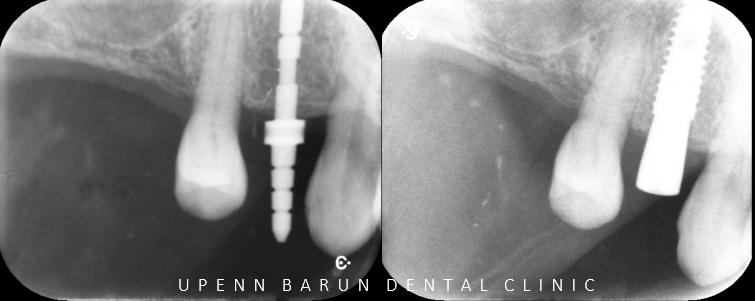

Periapical x-ray #14

유펜바른치과는

임플란트의 위치, 높이, 간격을 고려해

수술 중과 수술 후에도 작은 엑스레이를 통해

확인합니다 ^^

이처럼 더 안전하게 더 정확하게 잠실새내임플란트를 진행하고 있는데요